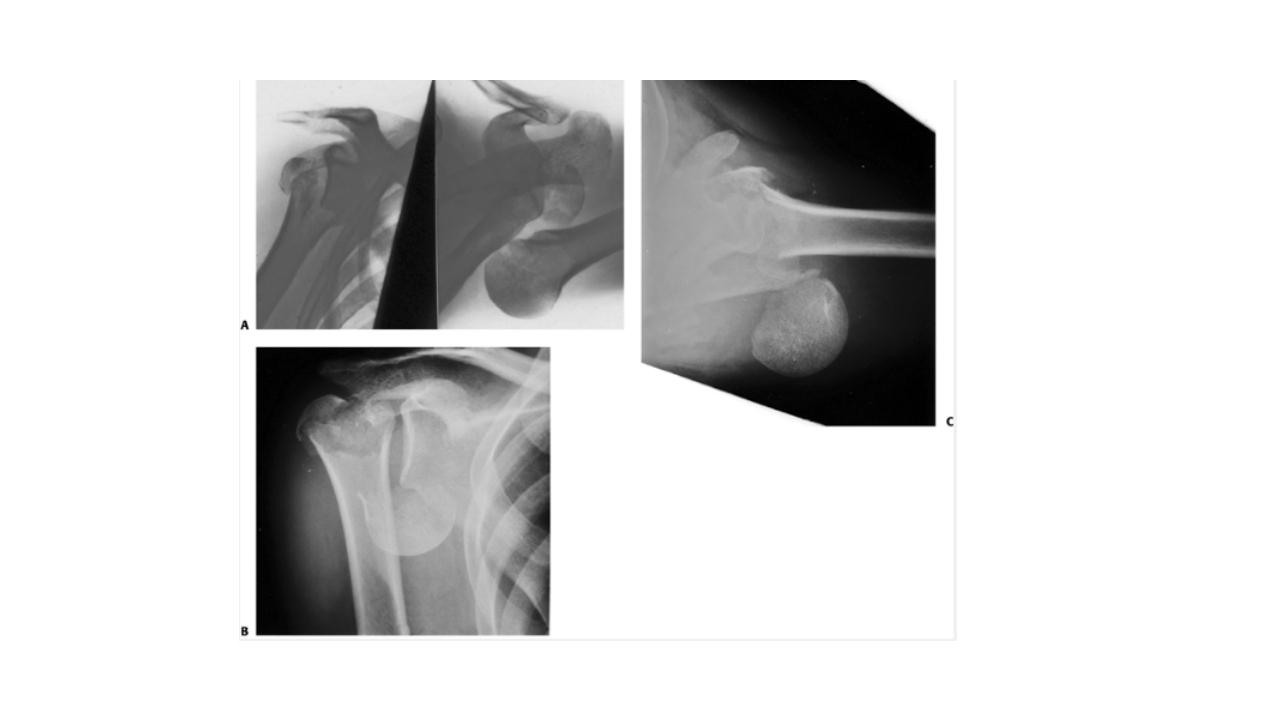

BUSINESS REPORT 肱骨外科颈骨折 汇报人:XXX 202X 汇报时间: 一 病史 主 二 解剖 要 三 病因 四 诊断和鉴别诊断 内 五 并发症 容 六 治疗 七 洗手巡回配合 (一) 病史 XXX,女,65岁,骨一科,+8床,391109,患者自诉不慎跌倒致 左肩部外伤疼痛,肿胀,活动受限,休息后无缓解,现来我院摄 X线片示:左肱骨外科颈骨折,予以收住入院。病程中无昏迷、 呕吐、畏寒发热。无逆行性遗忘。 (一) 病史 体温 36.4℃ 脉搏 76次/分 呼吸 20次/分 血压 100/80mmHg 一般情况 发育正常,营养良好,体型正常,神志清楚。皮肤、 粘膜温度正常,干燥,未见黄疸、皮疹或出血点。 患者于2012年10月8日9:00在臂丛神经阻滞麻醉下行左肱骨外科 颈切开复位内固定术,手术顺利,于10:...